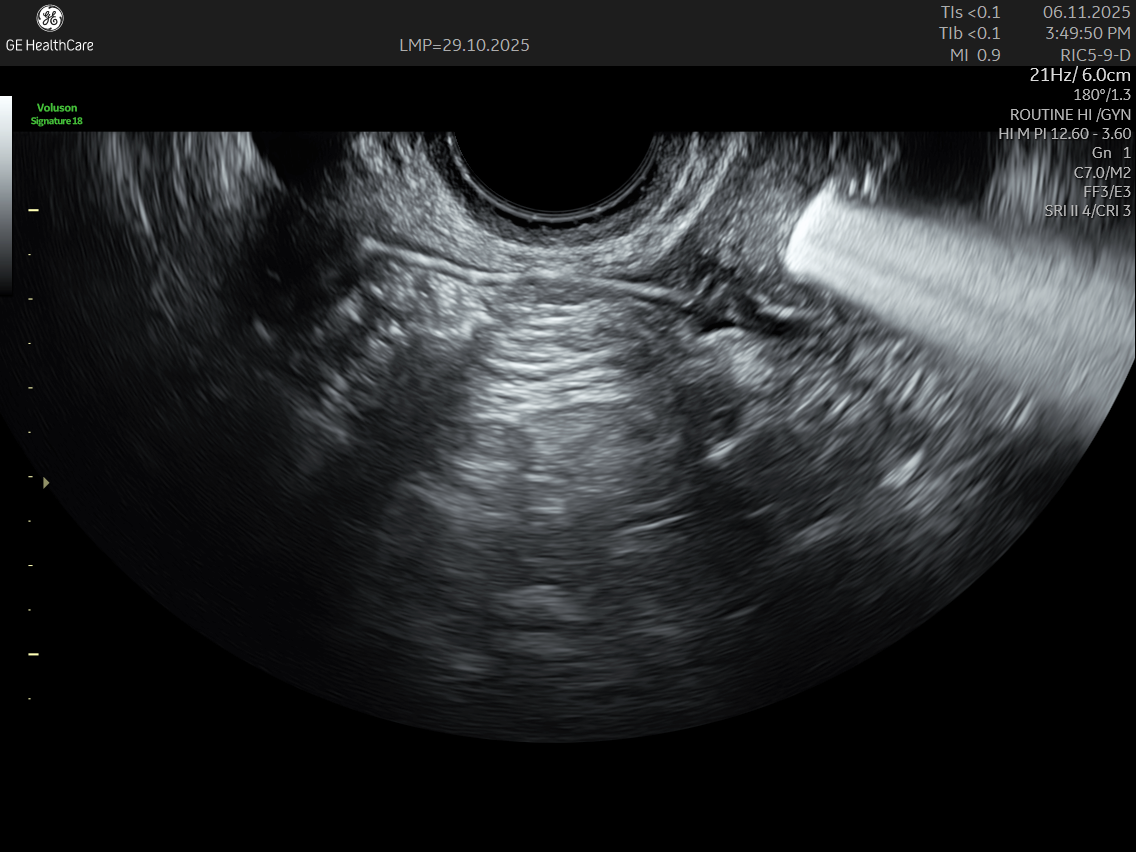

IMAGE GALLERY